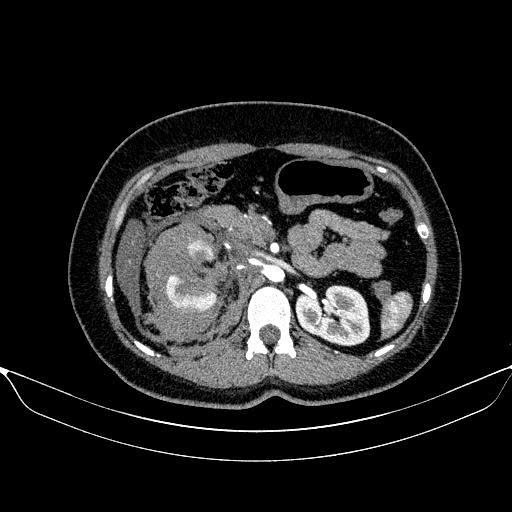

Ngay sau khi nhập viện, bệnh nhân được thăm khám khẩn trương và chỉ định thực hiện siêu âm ổ bụng, chụp CT sọ não và CT bụng có tiêm thuốc cản quang. Kết quả chẩn đoán hình ảnh cho thấy bệnh nhân bị vỡ thận phải độ IV theo phân loại AAST 2018 – một tổn thương nặng, có nguy cơ cao phải cắt bỏ thận nếu không được xử trí kịp thời.

Trước tình huống cấp cứu phức tạp trong thời điểm đặc biệt – ngày đầu kỳ nghỉ Tết, kíp trực cấp cứu đã lập tức mời hội chẩn khẩn cấp giữa Khoa Chẩn đoán hình ảnh & Y học hạt nhân và Khoa Ngoại tiết niệu. Sau khi đánh giá toàn diện tình trạng lâm sàng và hình ảnh học, các bác sỹ thống nhất lựa chọn phương pháp can thiệp nội mạch chọn lọc nút mạch cầm máu nhằm bảo tồn tối đa chức năng thận cho bệnh nhân thay vì phải phẫu thuật cắt thận như trước đây.